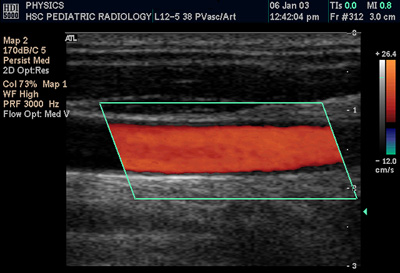

多普勒超声

多普勒超声大大提高了医学超声检查的能力,它利用多普勒效应判断某结构(通常是血流)是否朝向或背离探头运动,并计算出其相对速度。通过计算部分样本容积的频率漂移(例如心脏瓣膜上方的喷射血流),可以确定其方向、速度,并显示出来。这对心血管方面的研究特别有用,对其他的一些医学领域也是必要的,比方说诊断肝脏门脉高压症时的血流逆行。多普勒信息的图形化显示可以使用频谱多普勒,也可以使用彩色多普勒或者能量多普勒。通常此信息利用立体声扬声器表现出来:是一种虽然为人工合成,但是特征明显的声音。

在超声领域(但不是指信号处理领域),术语多普勒超声兼指脉冲多普勒和连续多普勒系统,而忽视速度测量的不同机理。

颈总动脉彩色超声多普勒声像图